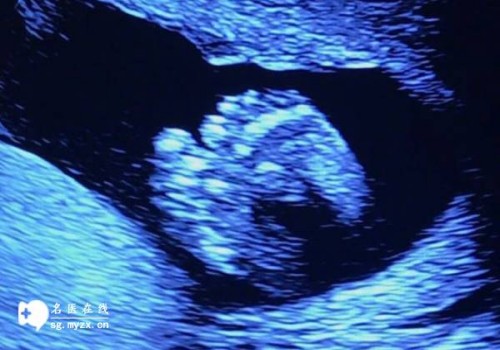

试管婴儿,又称体外受精-胚胎移植,是一种辅助生殖技术。其基本原理是将女性卵子和男性精子在实验室中体外结合,形成胚胎后再移植到女性体内进行着